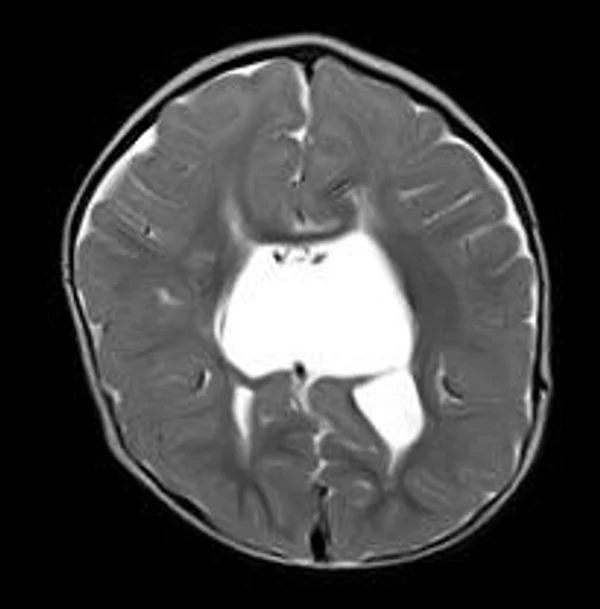

кисты, аномалии Денди-Уокера и др.Операции при внутричерепных кистах. В основном встречаются арахноидальные кисты различных локализаций и кисты сосудистых сплетений боковых желудочков. Пациентам с врождёнными кистами операции проводятся в следующих ситуациях: увеличении объема кисты в динамике, наличии клинических проявлений, компрессии и дислокации мозговых структур, наличии окклюзии ликворных путей. Нами используются 2 способа хирургического лечения кист: эндоскопическая перфорация стенок кист и открытая резекция кист. Открытая резекция кист проводится при ретроцеребеллярных арахноидальных кистах (рис. 2), при арахноидальных кистах межполушарной щели при отсутствии непосредственного контакта их стенок со стенками расширенных желудочков головного мозга и повторного увеличения кист средней черепной ямки после эндоскопической кисто-цистерностомии. Техника операции заключается в проведение краниотомии и максимальном иссечении стенок кист с созданием широкого сообщения кист с субарахноидальным пространством. Эндоскопические операции проводятся при арахноидальных кистах межножковой и пинеальной цистерн, арахноидальных кистах межполушарной щели при тесном контакте их стенок со стенками расширенной желудочковой системы (рис. 3), первично при арахноидальных кистах средней черепной ямки, а также при кистах сосудистых сплетений боковых желудочков. При арахноидальных кистах межножковой цистерны эндоскопически проводится перфорация стенок кисты, сообщая ее с просветом III желудочка и межножковой цистерной – эндоскопическая вентрикуло-кисто-цистерностомия (рис. 4). При арахноидальных кистах пинеальной цистерны проводится перфорация кисты в передне-верхних её отделах с созданием сообщения полости кисты с просветом III желудочка – эндоскопическая кисто-вентрикулостомия. С целью предотвращения облитерации сформированного отверстия иногда в полость кисты под контролем эндоскопа вводится стент перфорированный на протяжении (рис. 5, 6). Эндоскопическая кисто-цистерностомия выполняется при арахноидальных кистах средней черепной ямки. При этом создается широкое сообщение кисты с базальными цистернами. При кистах сосудистых сплетений боковых желудочков проводится их вскрытие в просвет боковых желудочков – эндоскопическая кисто-вентрикулостомия. При множественных кистах проводится их хирургическое сообщение между собой – интеркистосмия